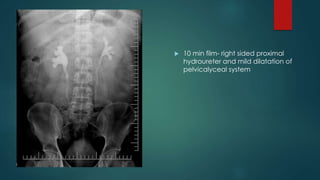

 10 min film- right sided proximal

hydroureter and mild dilatation of

pelvicalyceal system